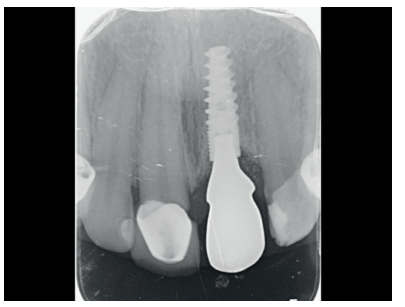

Se obtuvo una correcta estabilidad primaria, logrando un anclaje en el hueso residual palatino a un torque de inserción de 40 N/cm2 . Se realizó una radiografía periapical para confirmar la posición (Figura 10).